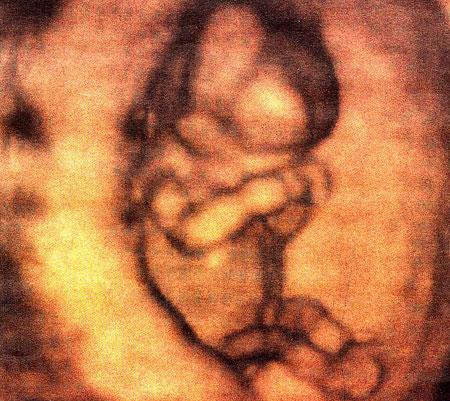

Ультразвуковые съёмки аборта на 12 неделе явно показывают: ребёнок чувствует боль, как любой из нас, и прекрасно понимает, что его хотят убить - он всеми силами старается отодвинуть от себя инструмент и широко раскрывает рот в безмолвном крике, когда у него отрывают сначала ноги, затем часть туловища…

Голову извлекают в последнюю очередь и лицо убитого ребёнка всегда искажено гримасой боли и ужаса. По этим кадрам видно, что практически нет разницы, убить ли 3-месячного ребёнка в утробе или отрезать руки -ноги -голову 5-летнему малышу. Без анестезии и в полном сознании.

- Фильм американского врача Бернарда Нэйтансона, названный «Безмолвный крик», показал всему миру, что такое аборт на сроке 11 недель беременности. Многие врачи и медсестры, посмотрев фильм, прекратили участвовать в абортах.

Это документальный фильм, и авторы рекомендуют соблюдать осторожность при его показе, поскольку некоторые кадры могут вызвать у человека психологический шок: безмолвный крик внутриутробного младенца, искаженное от боли лицо ребенка, погибающего на наших глазах...

Из закадрового текста к фильму: «Инструмент еще не коснулся ребенка, но он уже возбужден, его сердечные удары учащаются и достигают приблизительно 200 ударов в минуту. Вакуум-кюретка нащупывает ребенка, и он широко раскрывает рот в безмолвном крике».